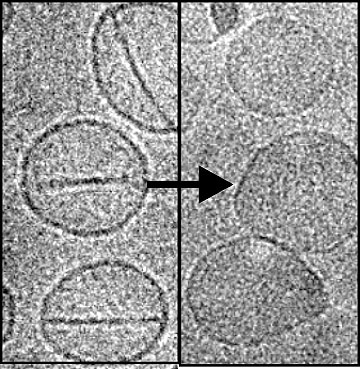

These second-harmonic-generation (SHG) images depict single optical sections of ex vivo human ovarian tissue. The malignant tumors are high-grade serous tumors as classified as pathology (left column). The field size in each case is 170 × 170 μm. The images were acquired at 40X 0.8 NA at zoom 2 using 890 nm excitation in the forward detection, isolated with a bandpass filter, and detected by a single-photon-counting photomultiplier.